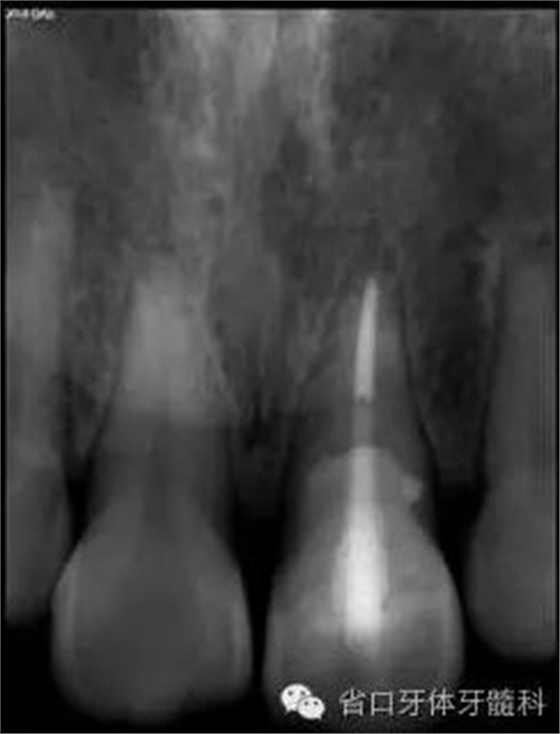

圖3. 術(shù)前X線片

圖8. 21/行根管治療術(shù),保留根尖約5mm的根充物,根中上段預(yù)留空間以預(yù)備纖維樁道。

圖17. 術(shù)后X線片